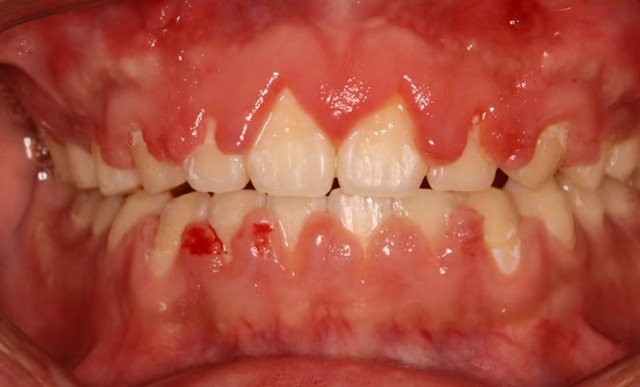

为了拥有整齐的牙齿和舒展的笑容,很多人选择了口腔正畸治疗。在与牙套亲密接触的过程中,有些人发现自己的牙龈变大变鼓了,按一按也不痛,还挺瓷实。这种情况被称为“牙龈增生”。

杨艳(副主任医师):牙龈增生主要发生在固定托槽矫正人群中。以我的个人经验,十年多前牙龈增生是比较多的,随着患者口腔清洁意识的提高,还有矫治器的更新换代,现在在成年人中已经不常见了,在儿童和青少年里发生得更多一些。

杨艳(副主任医师):牙龈增生对于矫正治疗没有明显的影响,它主要是影响美观,特别严重的可能会影响到咀嚼。

轻度的牙龈增生,一般在拆除托槽后可以逐步恢复。如果矫正治疗尚未结束,我们除了给患者强调要好好刷牙以外,还会给予药物牙膏和涂抹外用药物进行消炎治疗,并根据需要进行龈上洁治(洁牙),龈下洁治(刮除龈下结石)。

对于增生达到一定程度的患者,可以通过切除增生部分来治疗。